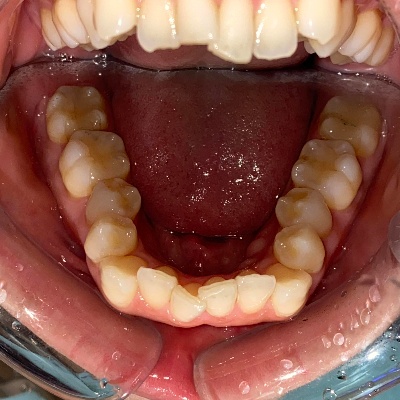

来院時の歯並び写真

上下前歯の歯並びがガタガタしているのが気になる、きれいにしたいとのご希望で来院されました。